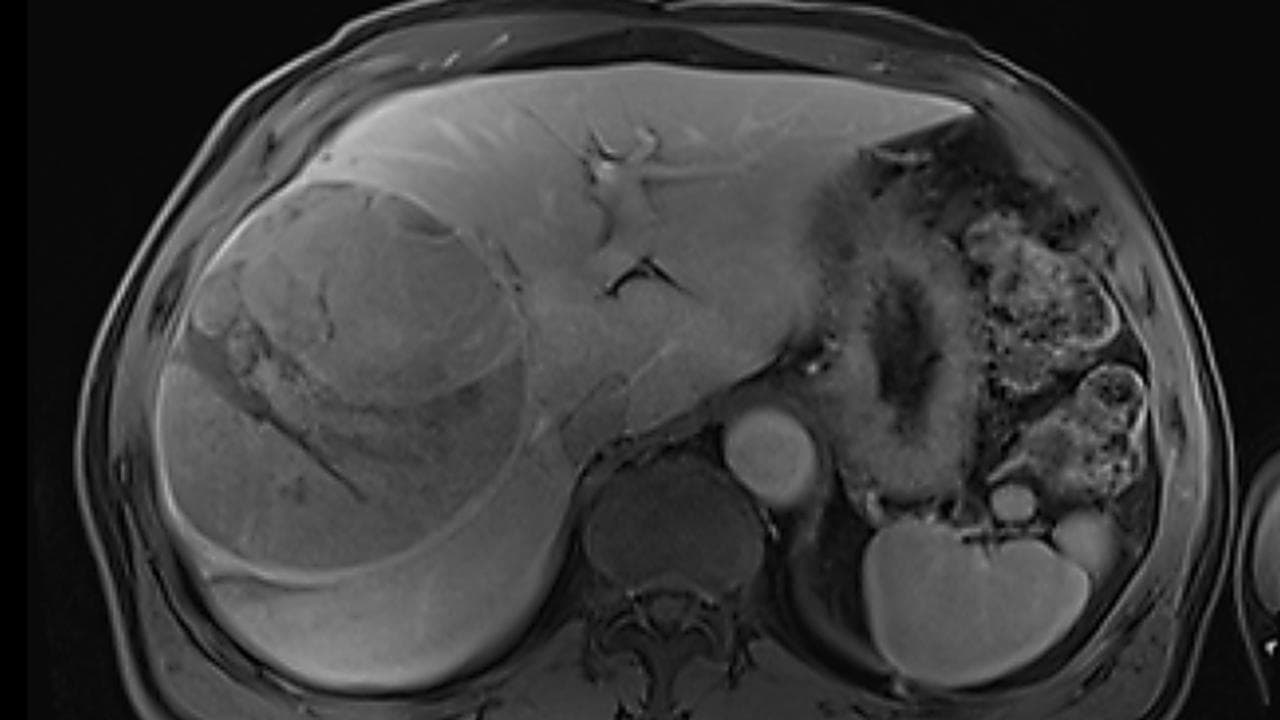

The 67-year-old was rushed to Mater Private Hospital in Brisbane to remove the 15cm aggressive hepatocellular carcinoma (HCC) tumour.

“I had more scans just before having surgery and the mass had become so large it was creeping up into my diaphragm," Mr Tibbetts said.

“The tumour occupied the majority of the right side of the liver, making surgical resection challenging,” Dr Lewin said.